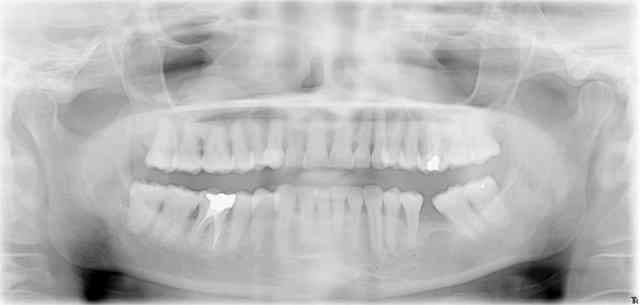

Ce genre d'image est assez fréquent. Cela peut être associé à des doléances sinusiennes, souvent chroniques, mais pas toujours. Il n'y a pas toujours d'endo en-dessous. Quoiqu'il en soit, on pense bien sûr à l'aspergillose (surtout avec "dépassement de pâte").

Pour ma part, j'envoie toujours la radio et un courrier au médecin traitant. Quand il daigne me répondre, il me parle souvent de "banal kyste muqueux", mais certains finissent tout de même chez l'ORL.

D'abord, reprise du traitement canalaire, mise en place d'une dent provisoire si t'es pas sûr, attente cicatrisation et ça devrait cicatriser à tes bons soins (par contre, ça peut mettre du temps)...

ça aurait évité de déranger un ORL (qui va opiner du chef ou d'autre chose) et le scanner (qui sert à quoi dans ce cas ??).

En l'absence de signe fonctionnel ORL , je n'envoie plus les images sinusiennes .

" On ne traite pas les radios " me disent les ORL .

Après , faut voir quels sont les signes dentaires ...